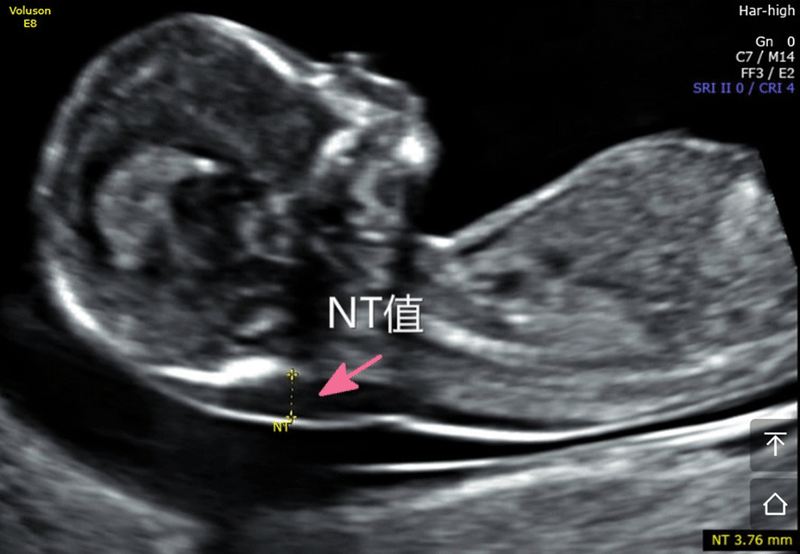

nt是胎儿颈后透明袋的简称,全称为(nuchal teanslucency),nt检查就是胎儿颈后透明带检查,检查胎儿颈后部皮下组织内液体积聚的厚度。

nt检查的主要作用就是获得nt值,通过nt值诊断胎儿是否正常,是否有染色体疾病和其他原因造成胎儿畸形,如果通过nt值提示胎儿有异常,在做四维彩超和唐氏筛查的时候将会重点关注。

nt检查正常值

nt检查正常值一般是在≤2.5mm,只要通过nt检查发现nt值在正常值范围内,就可不用担心了,nt检查属于一次检查。

nt检查方法:nt检查是通过超声波扫描进行检查的,在B超科室进行;

nt检查医生要求:在进行nt检查时,医生需要通过B超仪器讲胎儿引导至正矢位,让胎儿侧脸面对镜头,面部朝上,最好是在胎儿睡觉的时候进行扫描;